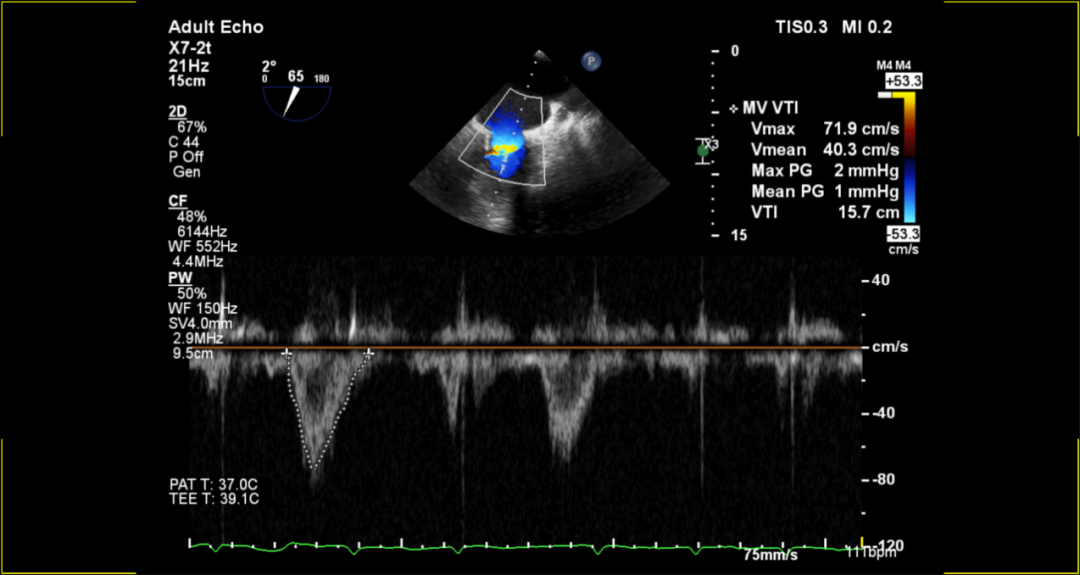

术后超声评估:

术后无反流、左室流出道通畅